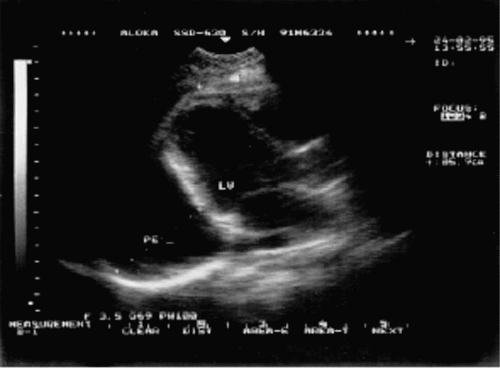

| Рис. 12.9. Двухмерная эхокардиограмма у больного со значительным количеством выпота Одномерная эхокардиограмма при выпотном перикардите. Отмечается уплотнение и умеренная сепарация листков перикарда |

При умеренном количестве выпота величина эхонегативного пространства достигает 4–8 мм. Жидкость можно обнаружить не только за ЛЖ, но и за ЛП. При двухмерном исследовании максимальное количество жидкости выявляется в области верхушки.

Значительное количество выпота сопровождается появлением эхонегативного пространства (размером 9–20 мм и более) как сзади, так и спереди камер сердца (рис. 12.10). Возникает гиперкинезия свободных стенок ЛЖ и МЖП и другие нарушения.

| Рис. 12.10. Двухмерная эхокардиограмма у больного со значительным количеством выпота в полости перикарда (РЕ). Жидкость определяется за задней стенкой левого желудочка, в области верхушки сердца и перед правым желудочком | ||